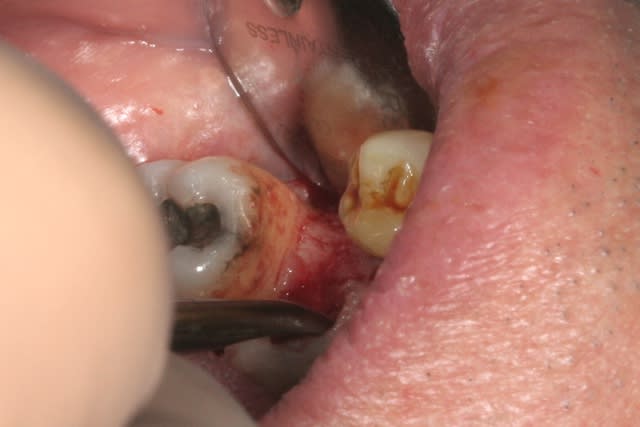

fin

mise en place de la vis de cicat basse pour augmenter l'épaisseur de gencive attachée et on suture par dessus...si çà s'operculise, c'est pas grave en plus